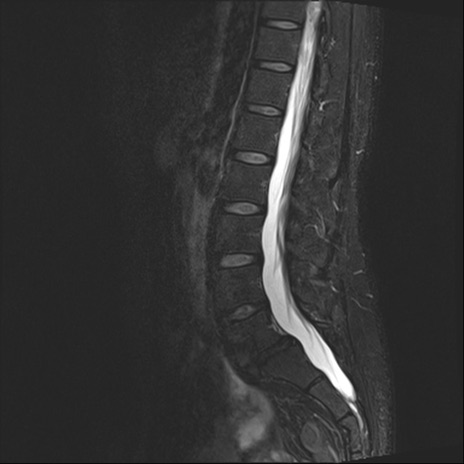

腰椎MRI

T2WI(矢状断像)